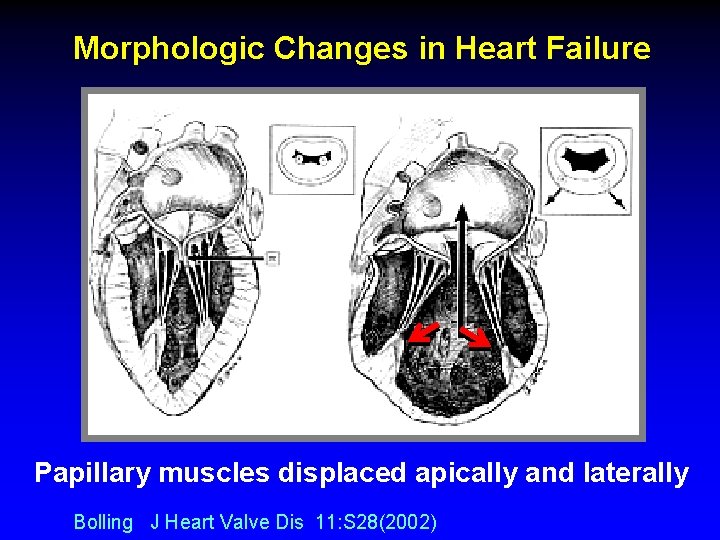

Morphologic Changes in Heart Failure Papillary muscles displaced apically and laterally Bolling J Heart Valve Dis 11: S 28(2002)